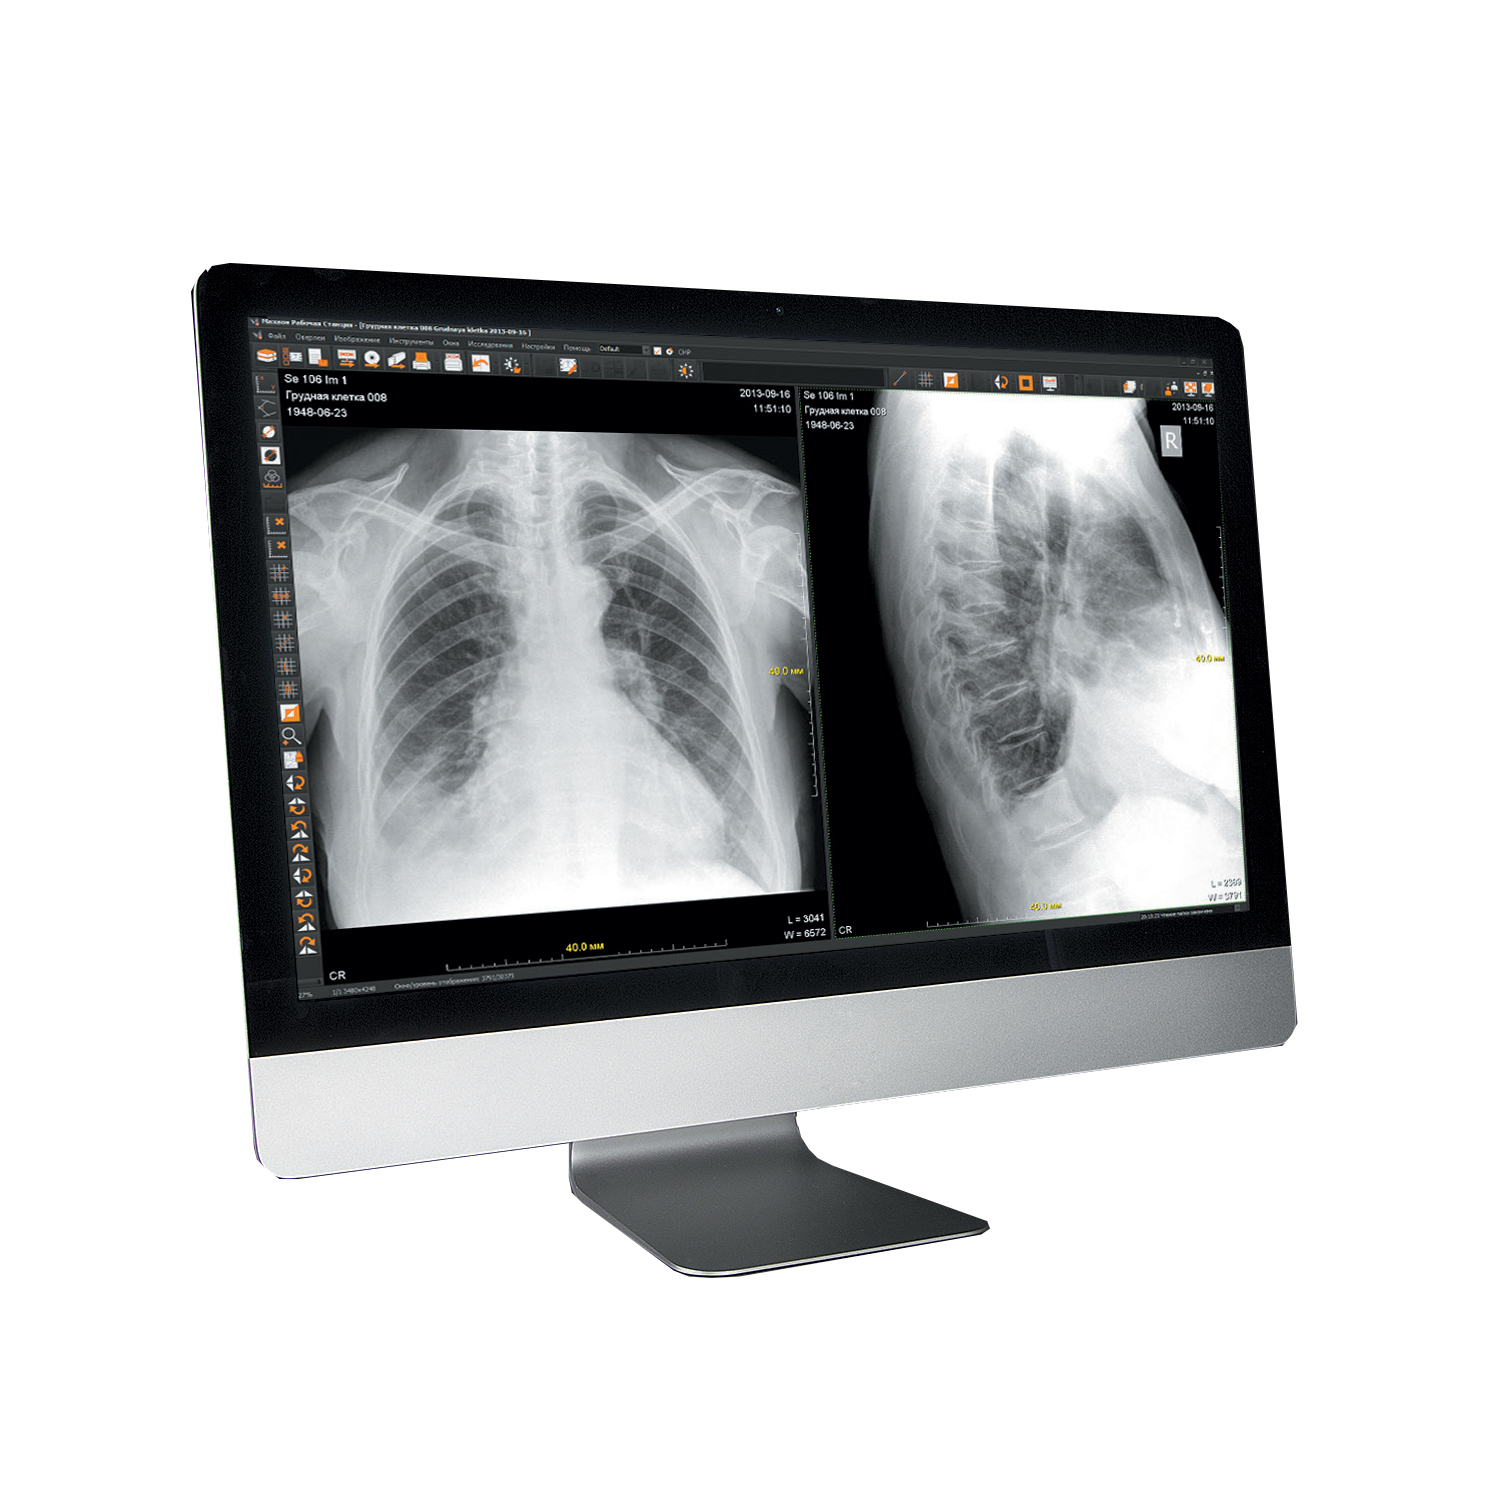

Организация рабочего пространства: стенды для рентгеновских снимков